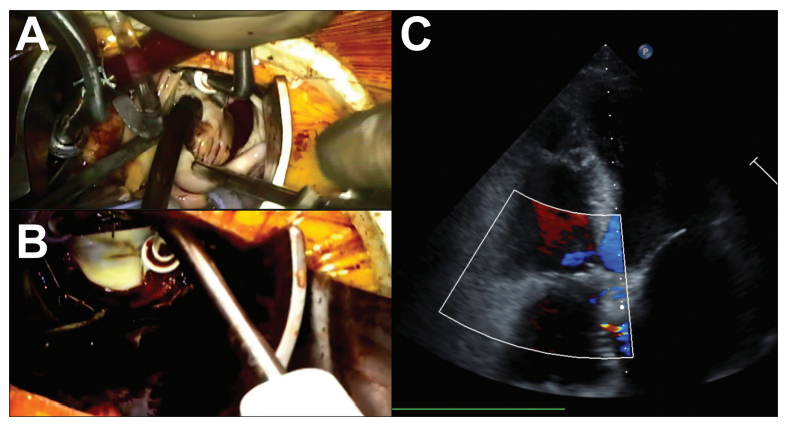

CPB在股静脉插管后开始,使用25-Fr两阶段(Edwards Lifesciences)插管进行上下腔静脉引流。在右内乳外侧的第四肋间进行一个4厘米的皮肤切口。然后使用Seldinger技术将主动脉套管(Edwards Lifesciences)放置在上升主动脉中。CPB开始后,用Bretschneider 心脏停搏液交叉夹闭后心脏停止跳动。在完全旁路中,打开右心房并取出封堵器。大型ASD允许进入左心房。左心耳从内部直接缝合闭合,并进行箱形病变冷冻消融。ASD用4×3厘米的自体心包贴片闭合(►图3A)。搭桥时间为136分钟,主动脉交叉钳夹时间为71分钟。使用28毫米的SimuPlus瓣环成形术在跳动的心脏入路中移除主动脉交叉夹后修复三尖瓣(►图3B)。移位的封堵器留在原位。总操作时间为213分钟。

图3. 术中图像显示了中央动脉插管和心房大面积暴露的手术入路(A)、跳动心脏入路中三尖瓣修复的最终结果(B)以及无三尖瓣反流(C)。

术中经食管超声心动图显示ASD已矫正,无残留分流和三尖瓣反流(►图3C)。患者术后临床效果良好,无并发症,术后4天出院回家。